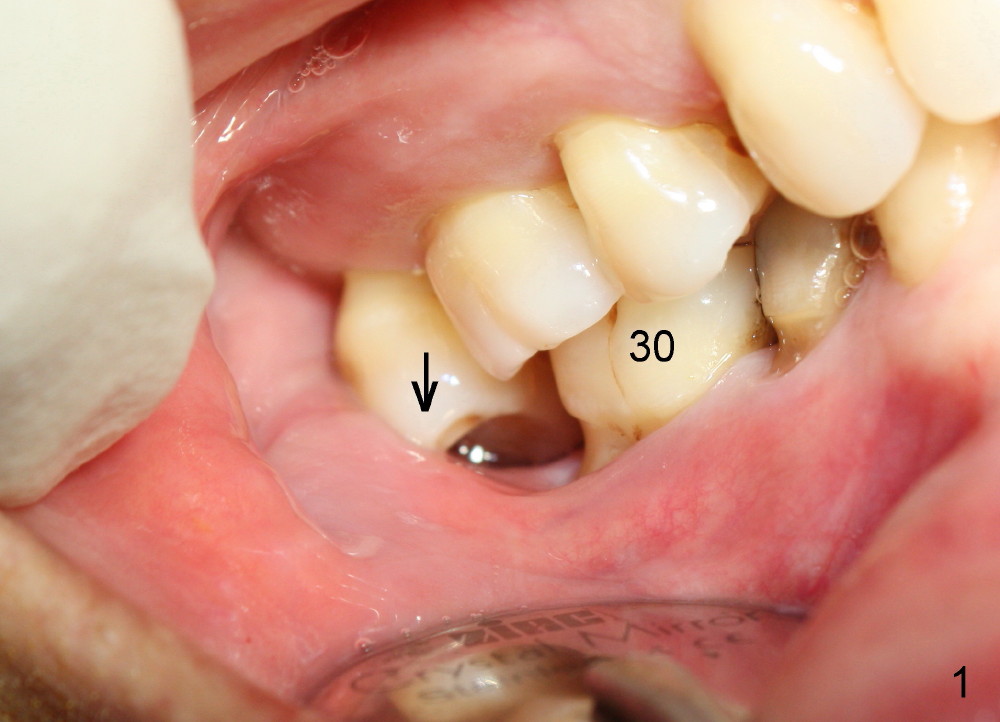

A 57-year-old lady returns for #31 implantation. The vertical edentulous space is limited, as the opposing tooth is supraerupted (Fig.1 arrow). Preop PA is critical (Fig.2), since it is used to measure the bone height (Fig.3: 12 mm). The length of the implant is expected to be 10 mm. The initial osteotomy depth is 8 mm (Fig.4); it appears that the trajectory should be adjusted. Osteotomy increases following depth and angulation adjustment (Fig.5: 4.5x10 mm drill). The submerged implant (5.3x10 mm) is placed with insertion torque approximately 35 Ncm (Fig.6). The buccal microthreads are exposed (Fig.7); to prepare for bone graft, the buccal plate is decorticated. Following placement of freeze dry mineralized allograft, collagen membrane is fixated by a healing screw (Fig.8). The incision is closed by 4-0 Chromic gut sutures and perio glue (Fig.9).

Bone-level implants offer two options after placement (stages 1 and 2). If the insertion torque is high and there is sufficient vertical edentulous space, a healing abutment is placed (stage 1). No surgery is required for restoration. Otherwise, the implant should be buried, as shown in this case. Two mini-implants are going to be placed to intrude the opposing supraerupted tooth. In fact, the orthodontic intrusion is quite difficult. Finally the intrusion apparatus has to be removed prior to chemotherapy for breast cancer. PAs taken 1 year 3 months (Fig.10) and 1 year 9 months (Fig.11, 6 months post cementation) postop appear to show that there is coronal bone loss. An abutment with short cuff (Fig.11 *) is chosen for final crown (C). Ideally the implant should have been placed deeper (Fig.7) for easy restoration. Pre-op examination and diagnosis are critical.